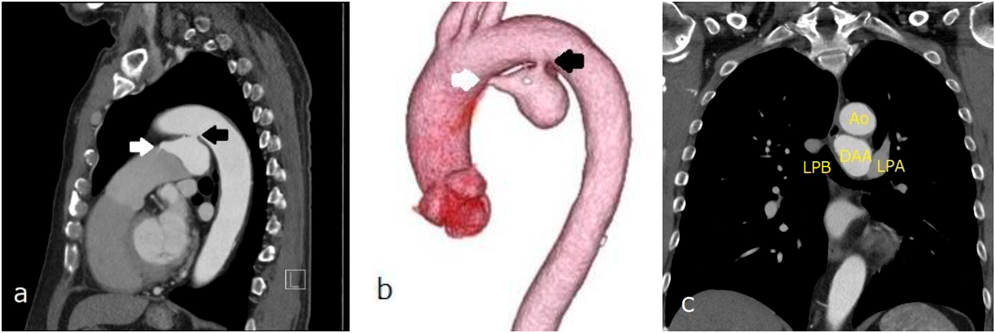

胸部造影CT

大動脈弓小彎側に入口部(径5.6 mm)をもつ最大径39 mの嚢状に拡大したDAAを認め,肺動脈側に出口部(2.2 mm)をもつ.大動脈解離なし.DAAは左主気管支と接触しているが圧排なし(Fig. 2).

Fig. 2 Contrast-enhanced chest computed tomography revealing a DAA with a maximum diameter of 39 mm, an aortic side opening measuring 5.6 mm, and a pulmonary artery side opening measuring 2.2 mm

A fistula from the minor curve of the aortic arch to the aneurysm is presented (a, b: black arrows). Drainage from the aneurysm to the main pulmonary artery is indicated (a, b: white arrows). The left primary bronchus was in contact with DAA; however, it was not compressed (c). Ao, aorta; DAA, ductus arteriosus aneurysm; LPA, left pulmonary artery; LPB, left primary bronchus.